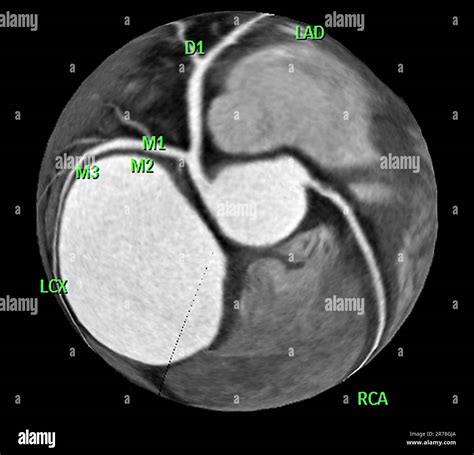

At its core, a Cardiac CT scan is an imaging test that allows cardiologists and radiologists to see if your coronary arteries are narrowed or blocked by plaque buildup—a condition known as atherosclerosis. Unlike traditional stress tests, which provide functional information about how your heart handles exertion, a cardiac CT provides anatomical information. It captures images of the heart while it is beating, using sophisticated gating technology to synchronize the image acquisition with your heart rhythm.

This technology is particularly effective at identifying early-stage heart disease before symptoms manifest. By visualizing the calcified and non-calcified plaque within the arterial walls, physicians can initiate preventative treatments far earlier than previously possible.

Once the scan is complete, the images are sent to a radiologist or a specialized cardiologist who analyzes the anatomy of your coronary arteries. They will look for the presence and extent of plaque, the degree of arterial narrowing (stenosis), and the presence of any calcium deposits. You will receive a formal report, and your primary doctor will discuss the findings with you to determine the next steps in your care plan. Depending on the findings, these steps may include lifestyle modifications, cholesterol-lowering medication, or further diagnostic testing.